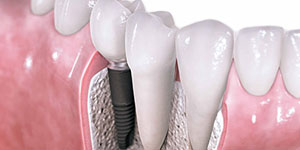

Implantologia

O implante dentário é um dispositivo médico concebido para substitu...

Implantes dentários

Um novo conceito na estética oral